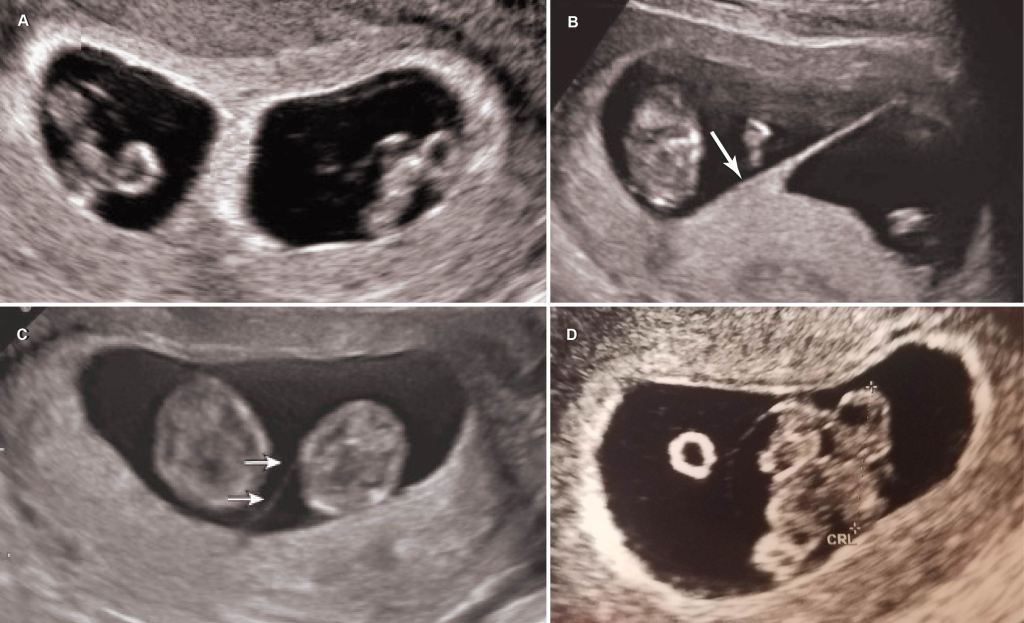

The short answer is no, most monoamniotic twins are not going to spontaneously die from cord entanglement. The truth is, entanglement of the umbilical cord is expected in 100% of momo gestations (Dias et al., 2010)(Fig. 2). Constriction of the cords, not just entanglement, is the real threat to momos, but not all cords become so tightly knotted. Most prenatal mortality before 20 weeks results from twin-reversed arterial perfusion (TRAP), discordant anomalies, spontaneous miscarriage from developmental anomalies, conjoined twinning, and complications from prematurity, but not from cord entanglement itself (Dias et al., 2010; Rossi and Perfumo, 2013). Size discordance in monochorionic twins is a symptom of twin-to-twin transfusion syndrome (TTTS). If left untreated, it can lead to intrauterine death of both twins. The silver lining from expecting momo twins is that TTTS is five times less common in momos than in di-mos. This is likely due to the arterial connections present in the placenta of momos, but not typically in di-mos (Umer et al, 2003; Hack et al., 2009). However, congenital defects are more common in momos (Myrianthopoulos, 1975). So long as these congenital defects are not detected in the 20 week anatomy scan and the succeeding echocardiogram around 24 weeks, a family expecting momos can breathe a sigh of relief, for the outcome of developmentally normal monoamniotic twins after 20 weeks is likely to be positive. If the cords are twisted or even knotted to some degree, do not panic; it is not an automatic death sentence. However, do consider that as the fetuses grow in size, so too does the diameter of their cords. Therefore, the threat of any tangled and knotted cords becoming compressed occurs later in gestation. That is part of the reasoning behind delivering momo twins no later than 32-34 weeks. Fortunately, the number of spontaneous losses of momo twins has decreased since the improvement of monitoring practices toward a more intensive monitoring schedule (Roqué et al., 2009; Rossi and Perfumo, 2013).

In-patient vs. out-patient monitoring

What does intensive monitoring mean when you are expecting momos? At the very least, a mother of momos can expect non-stress testing (NST) every two to three days, coming and going to her monitoring appointments at her leisure. Depending on her hospital and obstetrician policies, she can otherwise expect NSTs two to three times a day with ultrasounds twice a week (Fig. 3). Such regular monitoring would require the mother to go inpatient. That means living in the hospital without discharge until the babies are born and the mother is fit to go home.